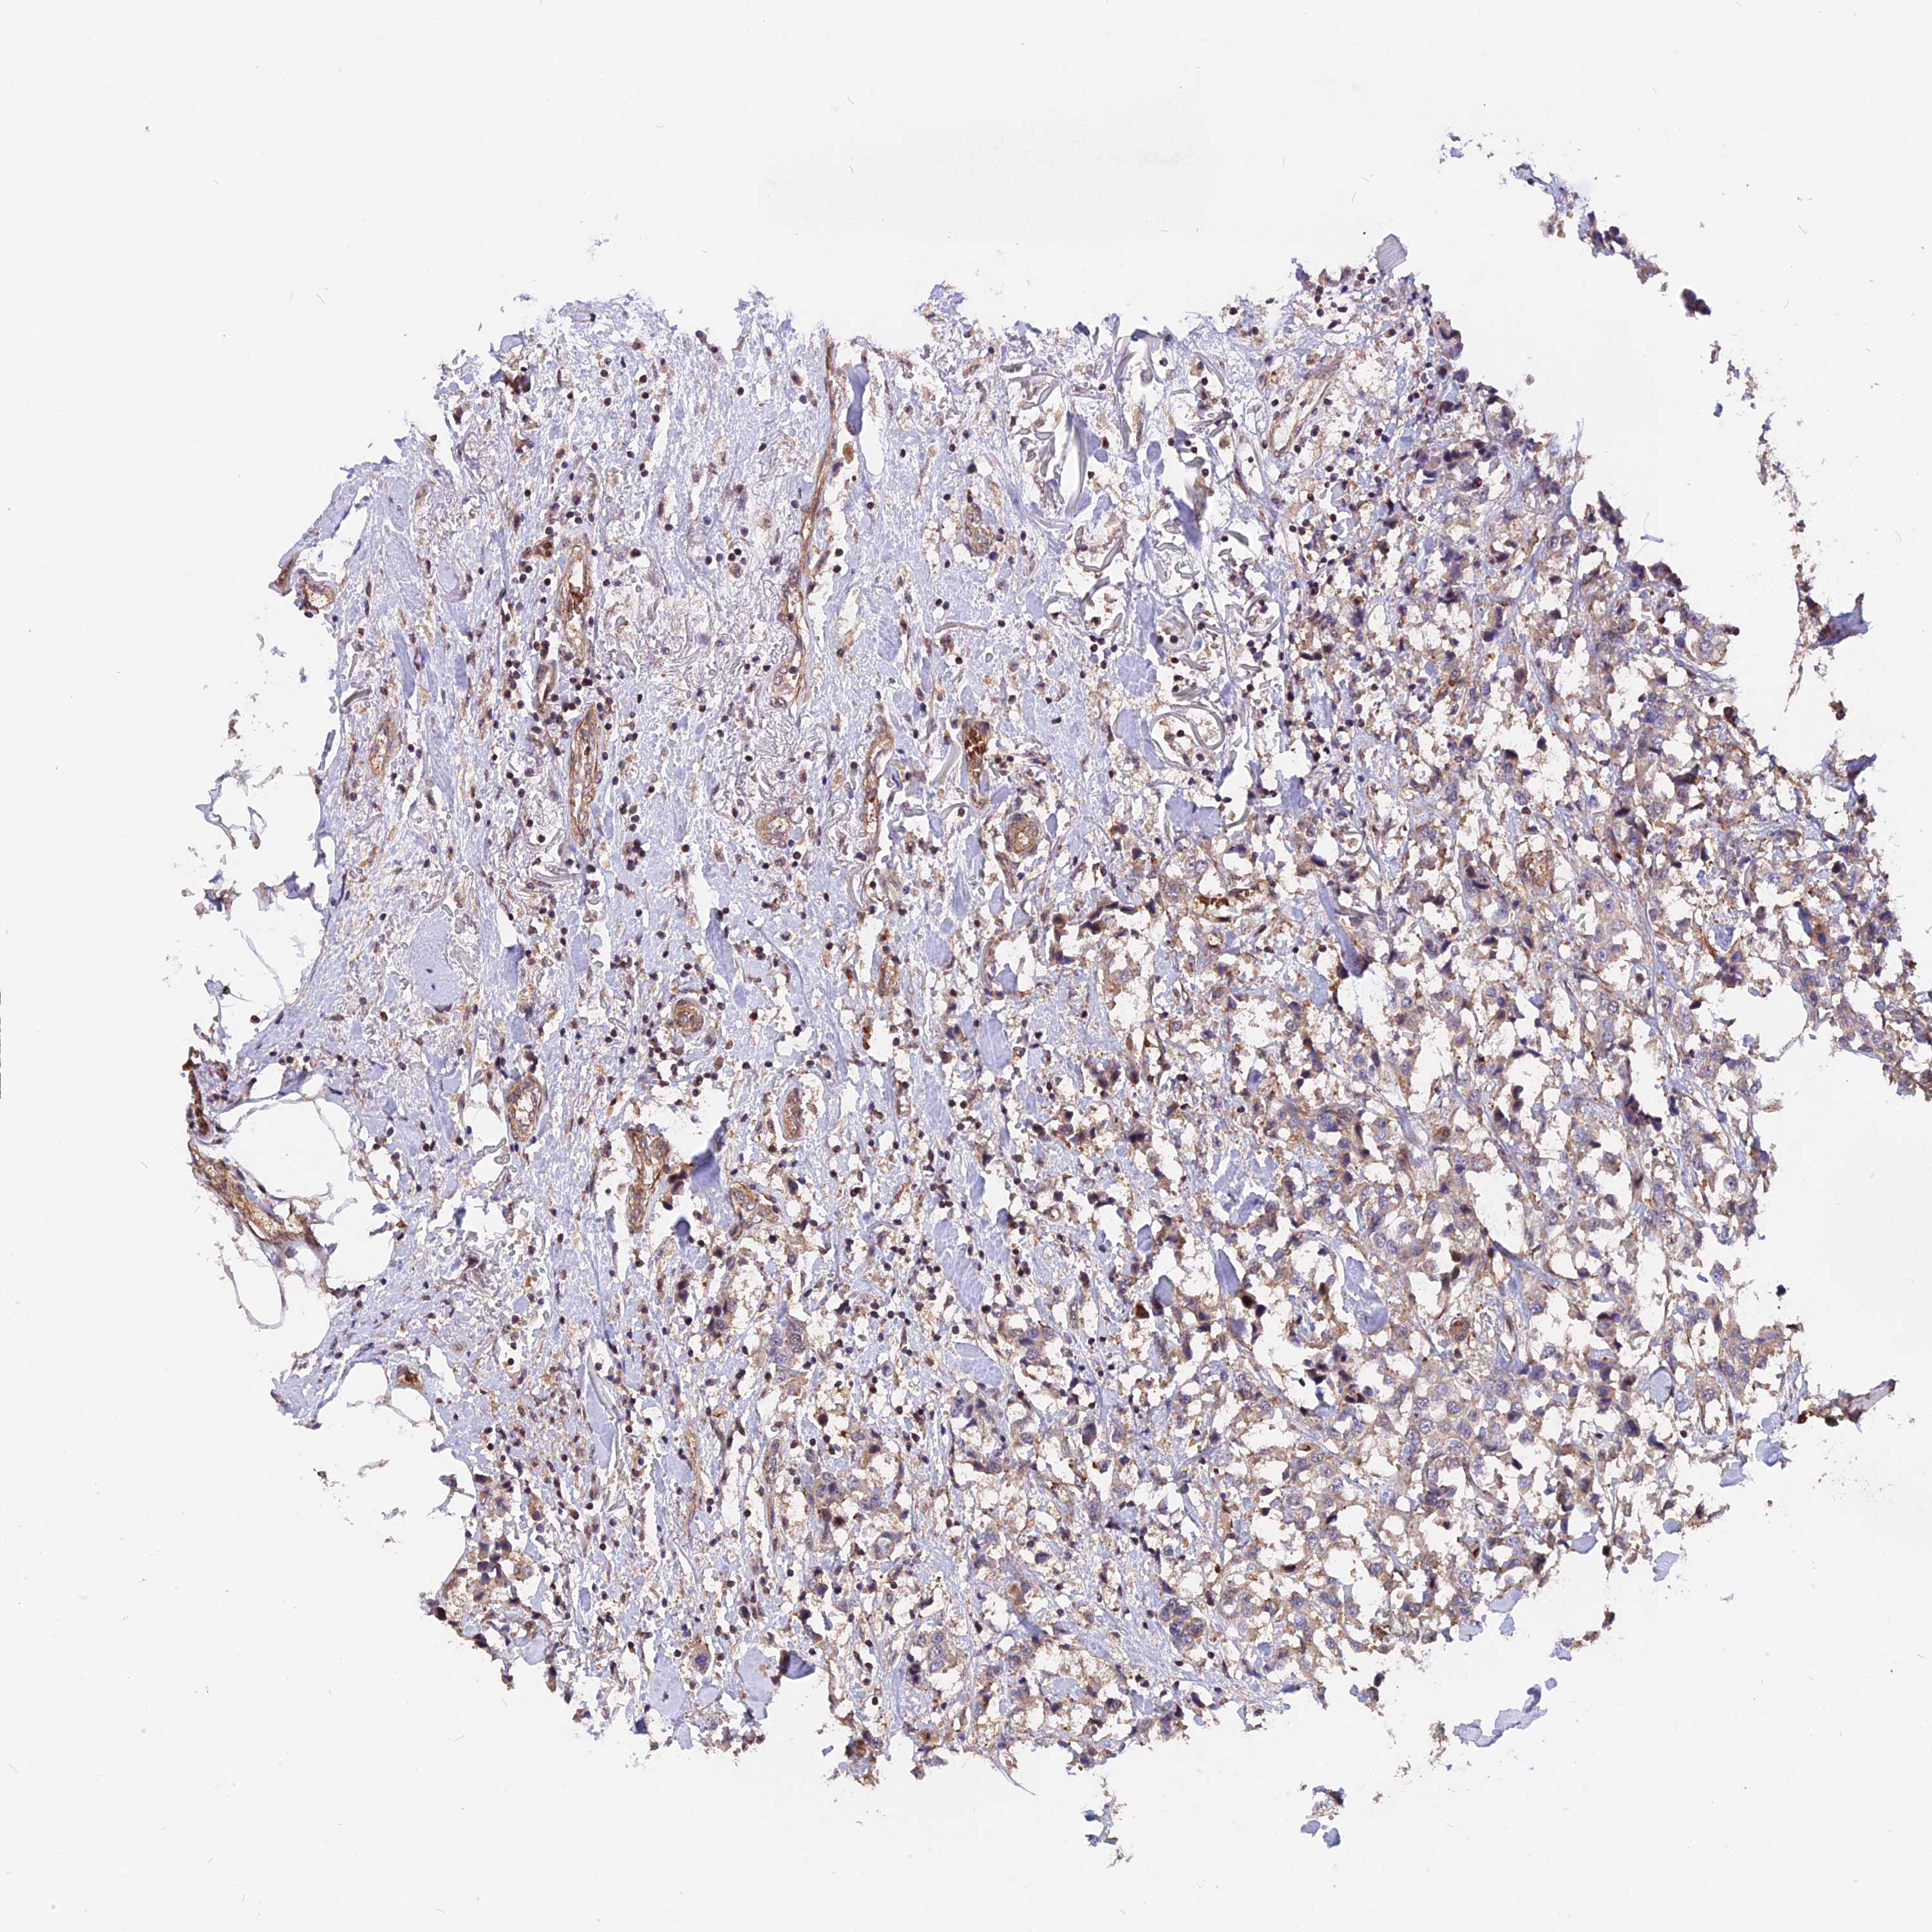

CANCER BREAST CANCER Show tissue menu

BRCA TCGA BRCA VALIDATION PROTEIN EXPRESSION

Breast cancer

Human cancer

Breast invasive carcinoma